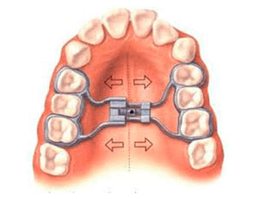

Rapid Maxillary Expansion

Orthodontic procedure used to widen the upper jaw in children and adolescents. This treatment corrects crossbites and creates space for crowded teeth by expanding the palatal suture.

Key Benefits

Corrects Crossbites

Creates Arch Space

Improves Breathing

Non-Surgical Approach

Early Intervention

Enhanced Facial Symmetry